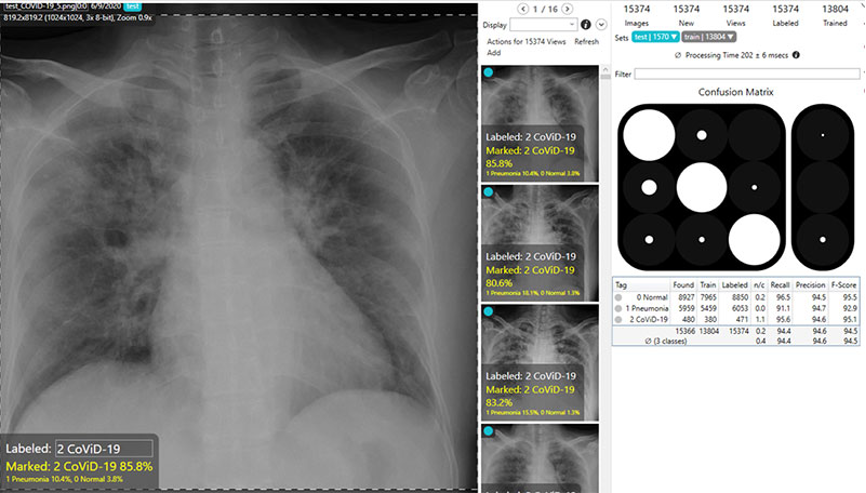

一項稱為F分數的測量對于深度學習系統的整體準確性進行了評估,該系統嘗試準確地預測數字圖像上的圖案和異常。康耐視的研究人員分析了COVID-Net數據集中的近14,000張X光片圖像。這些圖像被分為以下三種類型:正常、非COVID-19肺炎和COVID-19肺炎。

正如下面的表格中對多個深度學習軟件包進行的比較所示,COVID-Net產生了準確的預測結果,正常圖像為92.6%,COVID-19肺炎圖像為94.7%。VisionPro Deep Learning軟件的效果甚至更佳,正常X光片圖像為95.6%,COVID-19肺炎X光片圖片為97.0%。